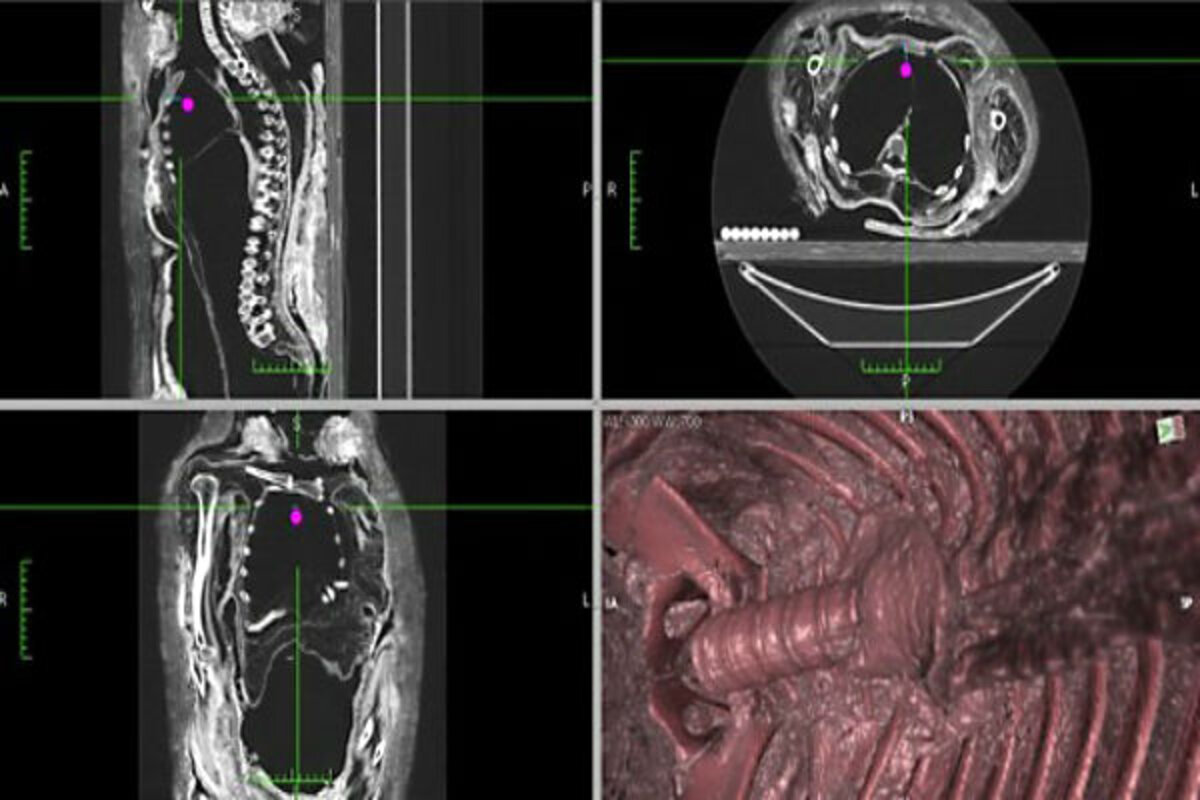

CT slices and 3D reconstruction showing the empty body cavity of the Royal Ontario Museum's ROM910.5.3 mummy.

To see how eviscerations really took place, Wade and his colleague Andrew Nelson looked through the literature, finding details on how 150 mummies were embalmed over thousands of years in . They also conducted CT scans and 3D reconstructions on seven mummies.